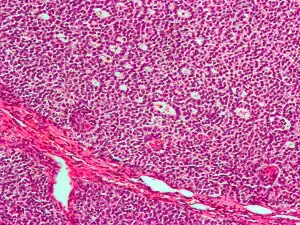

Micrograph of a granulosa cell tumour, a type of sex-cord–gonadal stromal tumour. H&E stain.

By prevalence

• Granulosa cell tumour. This tumour produces granulosa cells, which normally are found in the ovary. It is malignant in 20% of women diagnosed with it. It tends to present in women in the 50-55yo age group with post menopausal vaginal bleeding. Uncommonly, a similar but possibly distinct tumour, juvenile granulosa cell tumour, presents in pre-pubertal girls with precocious puberty. In both groups, the vaginal bleeding is due to oestrogen secreted by the tumour. In older women, treatment is total abdominal hysterectomy and removal of both ovaries. In young girls, fertility sparing treatment is the mainstay for non-metastatic disease.